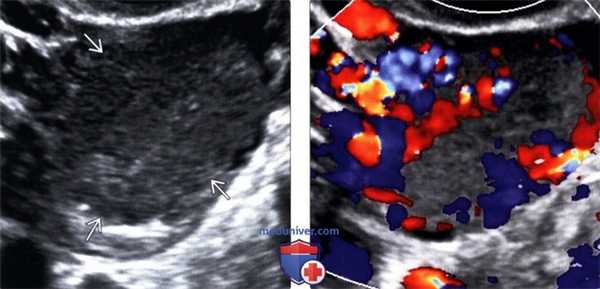

(Слева) КЖТ также может выглядеть солидной из-за кровоизлияния и спадения стенок кисты после овуляции.

(Справа) Цветовая допплерография: солидная КЖТ с усиленным кровотоком, визуально похожим на «огненное кольцо».